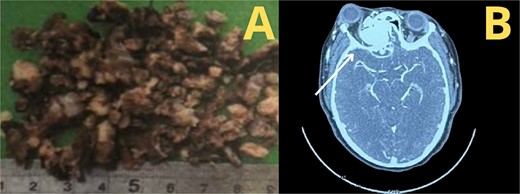

A tomography was performed to assess the extent of the mass inside the right nasal cavity. The imaging findings (Fig. 1) were consistent with a large mass (65 × 44 + 39 mm) originating from the right turbinates that was heavily remodeling the medial wall and the floor of the right orbit, compromising internal aspects of the maxillary and ethmoid bones; leading to a superior lateralization of the right eye causing exophthalmos.

Muscular and neural tissue were conserved intact but displaced.